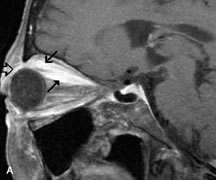

Tl relaxation time is the time required for the energized nuclei to give up the excess energy that was acquired from the RF pulse (high-energy state) and re-establish equilibrium (low-energy state) with the main magnetic field. The excess energy is released by these excited nuclei to the surrounding molecular environment, or lattice, and results in T1 relaxation, also called spin-lattice relaxation time. In different biologic tissues, hydrogen has a Tl ranging from a few hundred milliseconds to a couple of seconds. This range exists because local tissue factors affect the ability of specific protons to give up energy to the surrounding tissues. For example, hydrogen atoms attached to the carbon atoms of fat molecules relax much more rapidly than those attached to the oxygen atoms of water molecules. Viscosity, concentration, temperature, and molecular environment of the hydrogen atoms in the tissues also affect the T1 relaxation time. On a T1-weighted orbital image, fat, which has a very short T1 relaxation time, yields a high-intensity signal; the rectus muscles, which have an intermediate T1, yield an intermediate-intensity signal; and the vitreous, which has a long T1, yields a low-intensity signal (Fig. 8).5,8,16

Application of a 90° RF pulse brings the excited nuclei into phase so that the net vector of their magnetic moments is directed perpendicular to the static magnetic field. Shortly thereafter, the magnetic moments of the nuclei spread out and point in different directions, leading to a loss of phase coherence and a resultant decay in signal intensity amplitude. The T2, or spin-spin relaxation time, is the rate of decrease in the signal of these excited nuclei as a result of the interaction and transfer of energy to unexcited adjacent nuclei. T2 ranges from a few milliseconds to a few hundred milliseconds and, for a given tissue, is always less than the Tl relaxation time. T2-weighted orbital images are easily recognized by a high-intensity signal from the vitreous (Fig. 9).5,8,16

Contrast agents composed of paramagnetic or superparamagnetic materials can alter tissue properties to improve the MRI detection and characterization of certain pathologic lesions. Gadolinium diethylenetriaminepentaacetic acid (Gd-DTPA), the only paramagnetic agent currently approved in the United States for clinical applications, shortens the relaxation times of adjacent protons (hydrogen nuclei) and results in a bright signal on T1-weighted images. Gadolinium, like most heavy metals, is toxic in its nonchelated form but is safe when strongly bound to DTPA, which serves to eliminate its biologic toxicity. It is administered intravenously and is generally considered safer than iodinated radiographic contrast materials used for CT scans and arteriograms. It has little immunologic, systemic, and renal toxicity.20 Gd-DTPA has been shown to effectively detect disruption of the blood–brain barrier and delineate orbital tumors, such as meningiomas, gliomas, hemangiomas, and metastases (see Lacrimal Gland Tumors and Inflammatory and Lymphoproliferative Lesions in the section on Orbital Diseases). It also appears promising in identifying areas of altered circulation due to inflammation, ischemia, soft tissue injury, and neoplasia.7,8,21,22